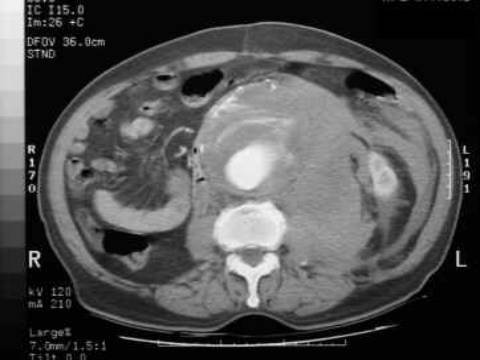

The abdominal aorta is the most common site of an arterial aneurysm. Abdominal aortic aneurysms (AAA) are usually located below the renal artery (infrarenal aorta).

The abdominal aorta is 1-3 cm in diameter in most individuals, and a diameter >3 cm at the level of the renal arteries is considered to be an aneurysm. Unlike thoracic aortic aneurysms, an AAA involves all aortal layers and does not create an intimal flap or false lumen. An AAA typically occurs in people aged >60 years and occurs at a higher rate in smokers, men, and people with a history of coronary artery disease.

Symptoms

Patients typically have few symptoms with AAAs, which are usually incidentally found on screening ultrasound or CT scan of the abdomen. Physical examination can reveal a pulsatile abdominal mass at or above the level of the umbilicus. Once the aneurysm ruptures, only about 50% of the patients survive to come to the hospital. They present with profound hypotension, abdominal or back pain followed by syncope, and possible pulsatile mass on examination. An AAA can rupture into the retroperitoneum and create an aortocaval fistula with the inferior vena cava, leading to venous congestion in retroperitoneal structures (e.g. bladder). The fragile and distended veins in the bladder can rupture and cause gross hematuria (as in this patient).